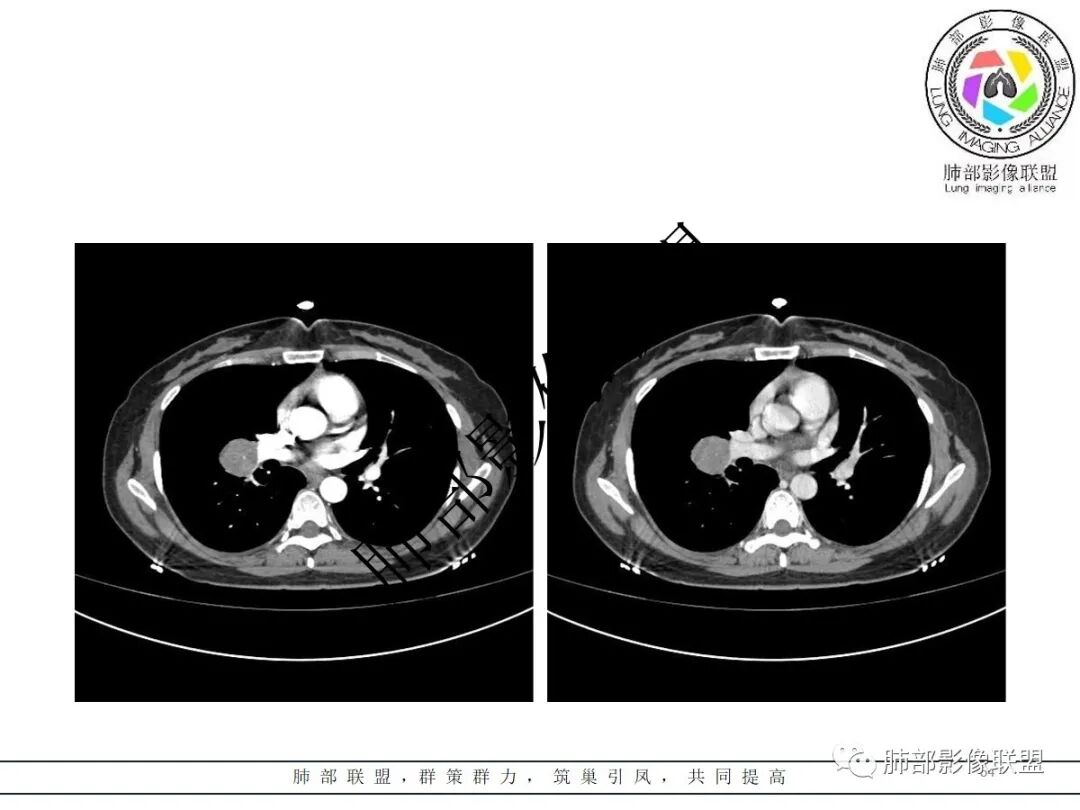

右肺门类圆形实性肿块,边缘光滑,无分叶毛刺,跨叶,推移血管,密度均匀,增强延迟强化相对明显,未见坏死及血管造影征。

右肺门区类圆形肿块,跨叶,边缘光滑,密度均匀,血管贴边,推移,延迟强化,考虑PSP,鉴别CD

2.右肺水平叶裂斜叶裂肺门交界区类椭圆形块影,表面光整,未见分叶毛刺及棘状突起,未见邻近结构牵拉。与邻近支气管无关联。

3.病灶密度均匀,未见液化坏死、钙化及脂肪低密度。轻度强化,可见纤细血管影蜿蜒穿行。右肺动脉推移变形,未见侵入或充盈缺损。

4.灶周未见磨玻璃晕或极低密度影环绕。右肺下叶背段胸膜下见微小实性密度结节影,边界清楚。

5.双肺门及纵隔未见增大淋巴结。双侧胸腔未见积液。